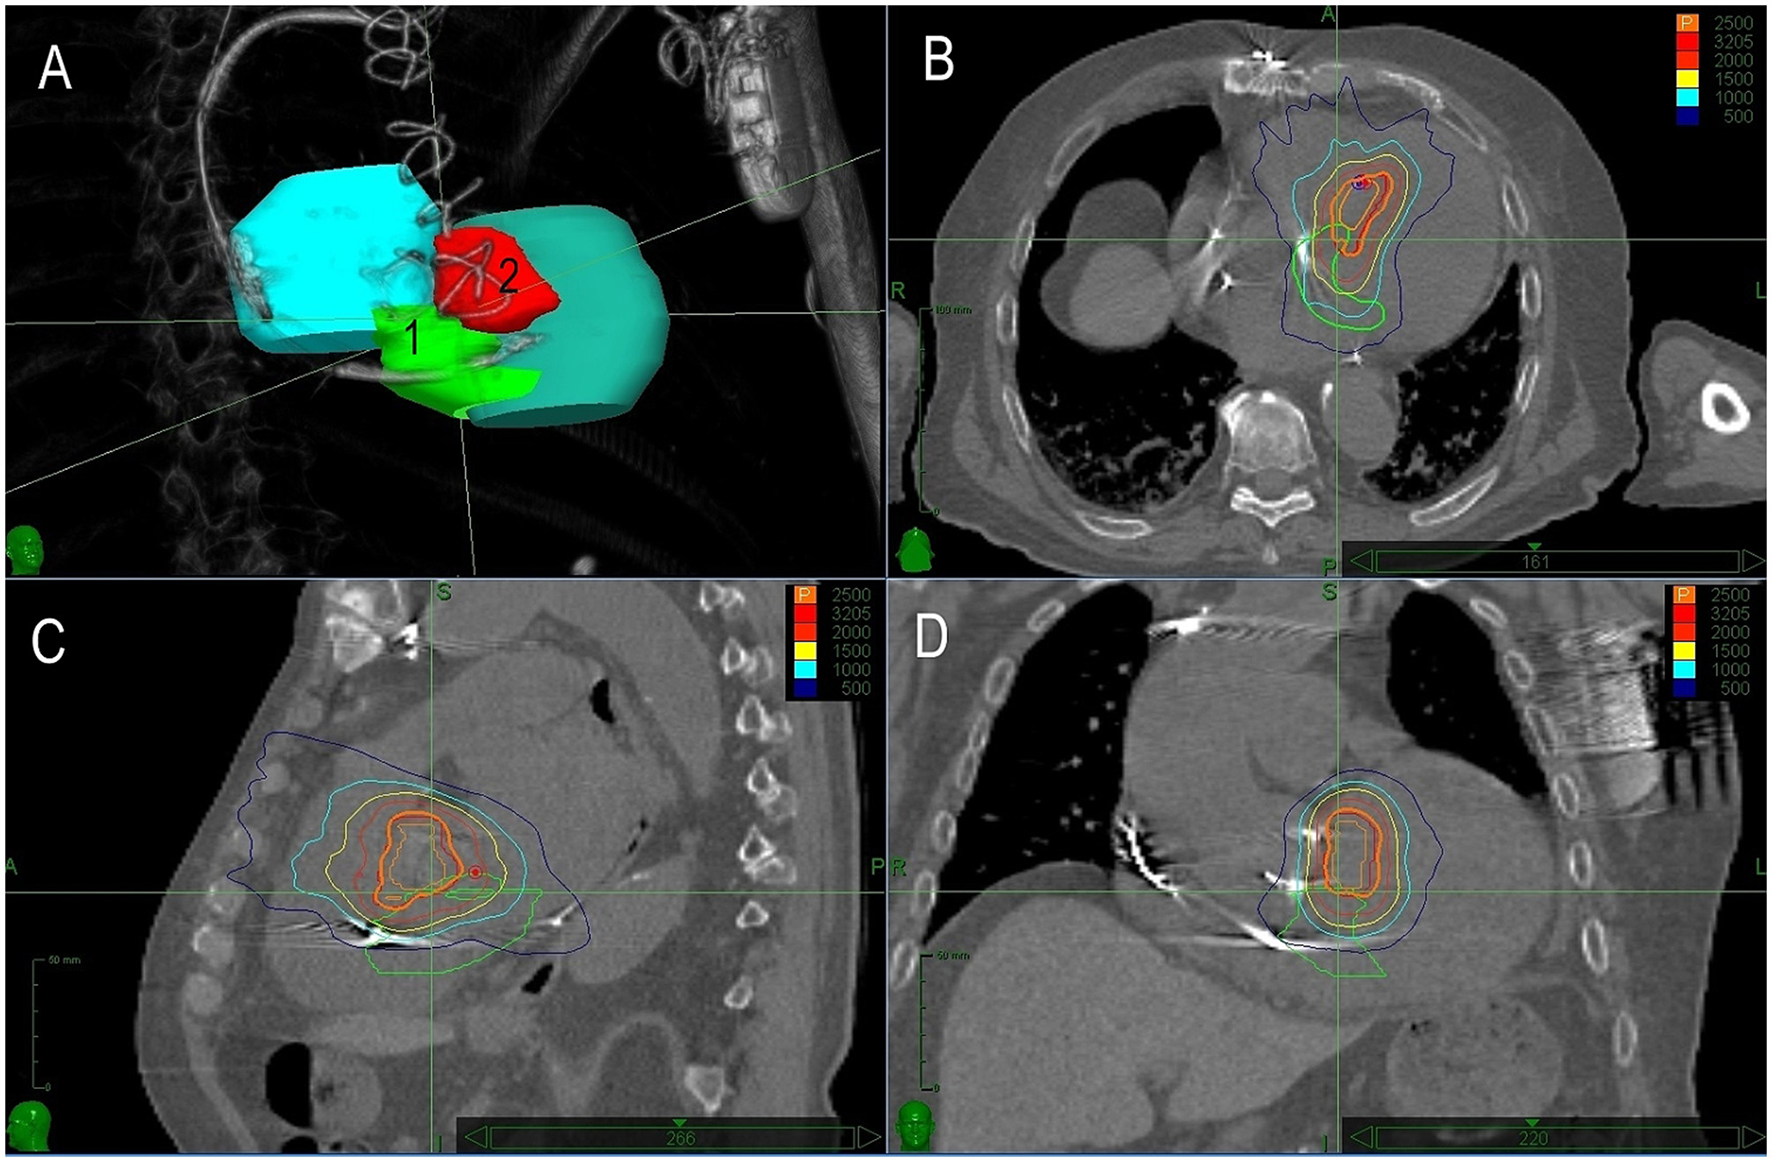

The third patient was a 77-year-old man with a diagnosis of non-ischemic cardiomyopathy and intramural location of fibrosis in the basal region of the left ventricle. The patient presented with ventricular arrhythmias for several years and was implanted with a single chamber ICD. Later, aortic valve replacement with mechanical prosthesis was performed for aortic regurgitation together with a concomitant MAZE procedure. After 3 years, the device was upgraded to cardiac resynchronization therapy-defibrillators (CRT-D). At that time, the patient presented with an electrical storm. They underwent electroanatomical mapping and substrate ablation in the inferoseptal region of the left ventricle two times. For sporadic recurrences of VT, the patient was referred for SBRT 1 month later (Figure 3). A 25 Gy dose was applied to the basal inferoseptal region. After temporary improvement, the patient presented with recurrent VTs and underwent 2 months later another electrophysiology study. Three different VTs were induced, all with the exit in the septum above the initially irradiated region. The entire basal septum showed decreased bipolar voltage and catheter ablation covered it all. No VT was inducible at the end of the procedure. The patient was readmitted for decompensated heart failure due to incessant VT with an exit in the upper septum and was indicated to re-do SBRT. The septal region adjacent to the initial PTV was delineated as a new PTV with minimal spatial overlap. The second SBRT was performed 4 months after the first one (Figure 4). After SBRT, the patient continued to present with slow VT (CL around 600 ms) which necessitated another catheter ablation from both sides of the interventricular septum. Non-inducibility of VT was achieved. Although the patient was without VT, their overall clinical status gradually deteriorated and then eventually died due to the progression of heart failure 1 month later. No autopsy was performed.

Figure 4

The treatment plan for Case 3. Description of (A–D) is identical as in Figure 1. In this case, the second planned volume covered extensive substrate within the basal septum.